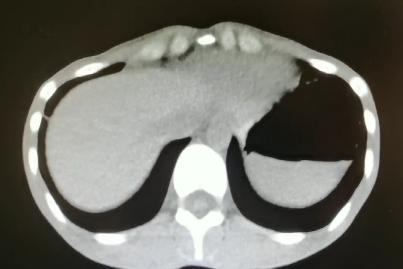

2021-4-29全腹增强CT:腹盆腔散在积液,上腹腔少量积气,腹壁软组织积气,盆腔置管影。肝实质灌注不均,肝内淋巴瘀滞,提示肝功能损害。右侧见一支副肾动脉;左肾动脉提前分支。双侧附件区见多房囊状低密度影,可见环状强化,囊肿?卵泡?或其它?

患者青年女性,慢性病程;主要表现为腹胀、呼吸困难,术后出现意识障碍、II型呼吸衰竭。经呼吸机辅助呼吸、对症支持等治疗后,患者意识恢复但呼吸困难无明显改善;既往有有粉尘接触史。查体见患者极度消瘦、营养不良,双肺呼吸音粗,可闻及散在湿啰音。血气示II型呼吸衰竭、高碳酸血症,轻度贫血,低蛋白血症,电解质紊乱,炎症指标、肌酶、BNP升高,院外腹水检查示漏出液,未见肿瘤细胞;胸部CT:双肺斑片影,抗感染治疗后病灶吸收;腹部增强CT:双侧附件区分别混杂密度团块影,内见多发囊泡影;心脏彩超:右心稍大,重度肺动脉高压。